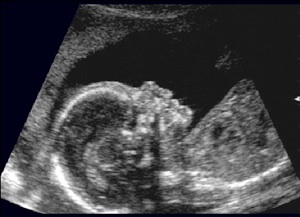

Nell’ecografia successiva (12°-13° settimana) invece il feto è quasi completamente formato, e sarà possibile evidenziarne gli arti, le estremità, stomaco e vescica. In questo periodo è bene valutare la translucenza nucale e la presenza delle ossa nasali.